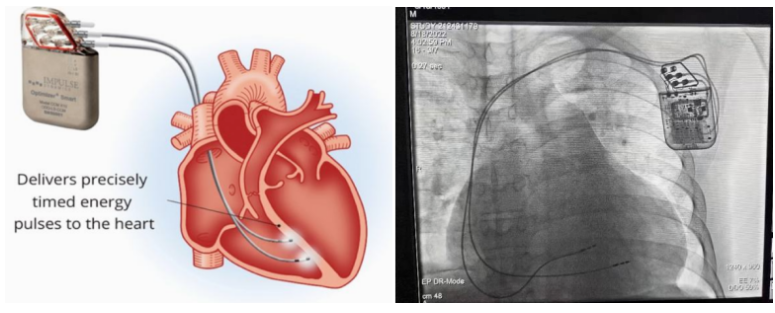

②心臟再同步治療

Cardiac Resynchronization Therapy,CRT

心臟再同步化治療,指雙心室起搏器,是通過雙心室同步起搏的方式,幫助心衰患者實現(xiàn)正常起搏的裝置。CRT包括一個口袋大小的脈沖發(fā)生器和三根電極導(dǎo)線,可被植入人體。通過監(jiān)測心律,在發(fā)現(xiàn)異常后,信號發(fā)生器發(fā)送電流脈沖,刺激心室重新同步,從而改善癥狀,提高患者的心臟泵血效率。目前有兩種類型的CRT裝置:植入式心臟再同步治療起搏器(CRT-P)和植入式心臟再同步治療除顫器(CRT-D)。主要區(qū)別在于后者除了改善心臟收縮同步性外,還具備除顫功能,能及時處理危及生命的室性心律失常,避免猝死。